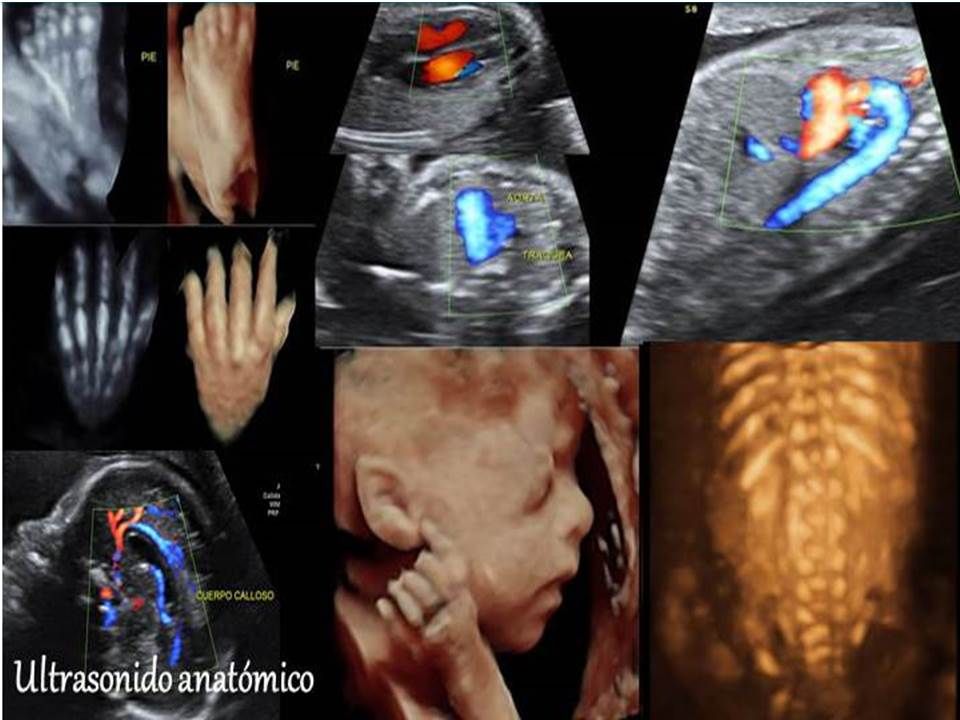

Ofrecemos los estudios de imagen necesarios para descartar malformaciones y para predecir el riesgo de enfermedades cromosomicas (como Sindrome de Down) y de complicaciones en el embarazo.

Contamos con el equipo que actualmente ofrece la mejor resolución disponible, tanto para hacer un diagnostico certero, como para que las futuros papás puedan ver una imagen mas realista de su bebe.

Ultrasonido obstétrico

Este tipo de ecografía, es la que se hace de manera rutinaria durante el control prenatal, en este estudio se valora el peso del bebe, como esta acomodado, la cantidad de líquido, localización de la placenta, y a partir de las 16 semanas, puede determinarse el sexo fetal con 100% de seguridad No es un estudio muy completo, y por lo que se recomienda realizar el ultrasonido anatomico entre la semana 20-24 para confirmar que el bebe se encuentre bien y descartar la presencia de malformaciones.